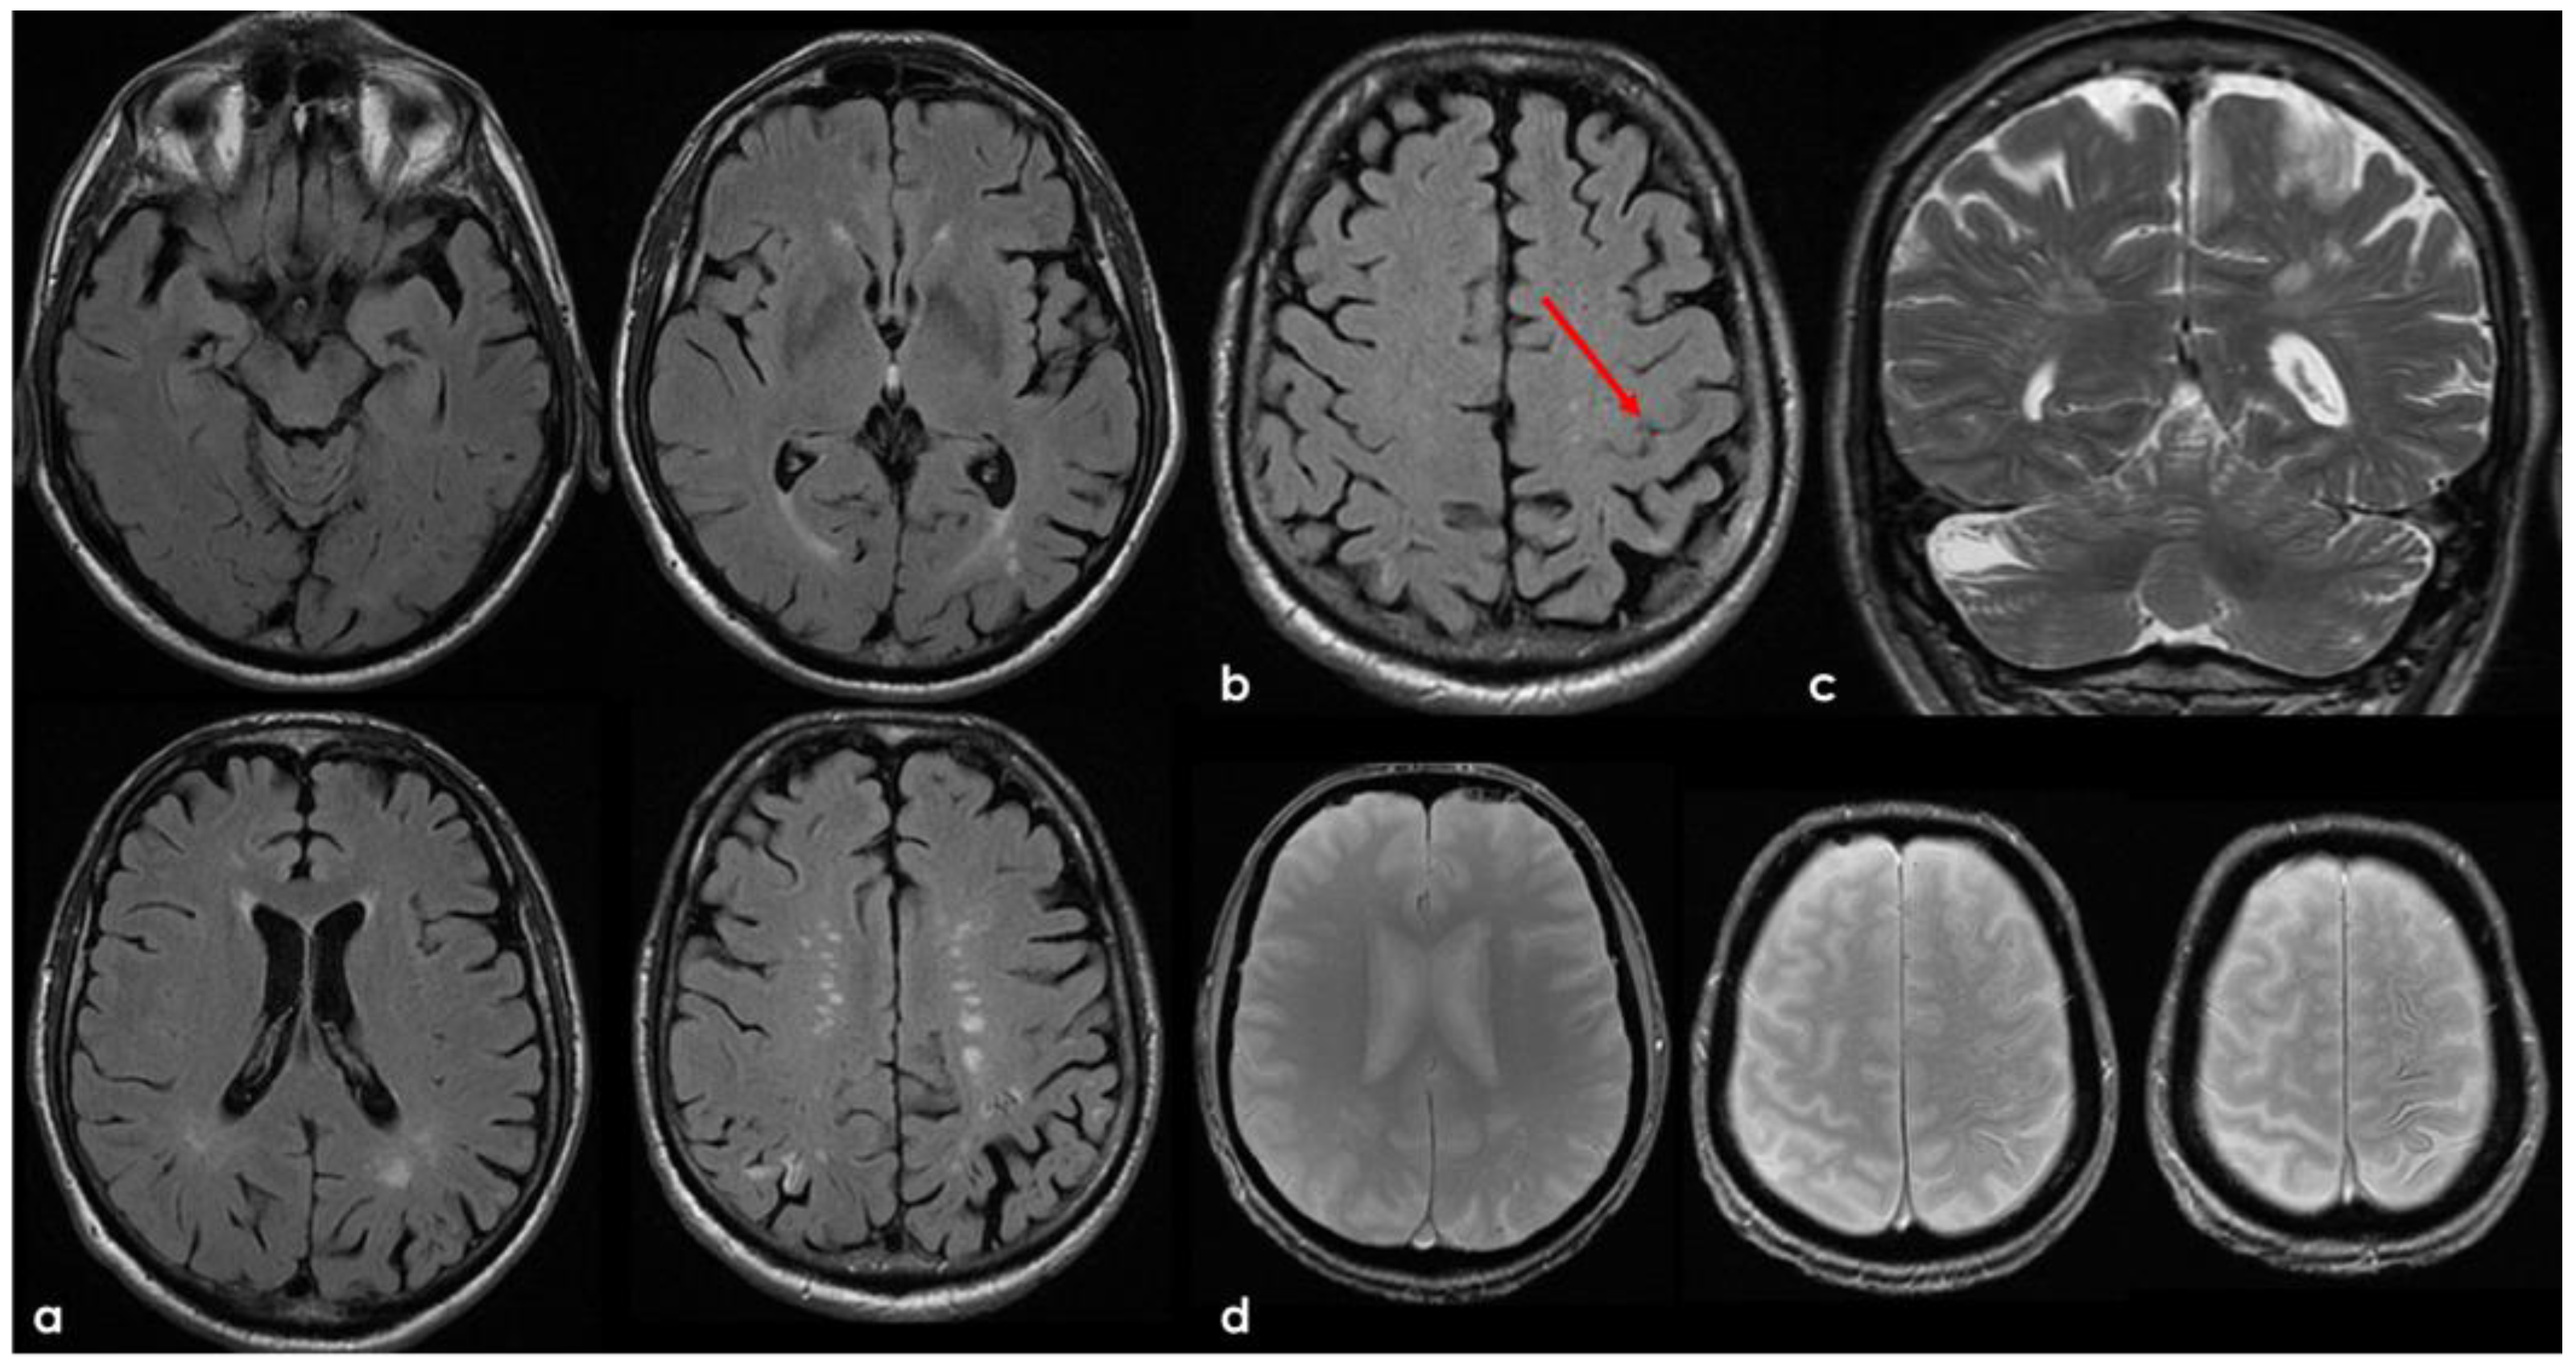

6. December 2017: Recurrent SAH

7. April 2018: Second Recurrent CAA-Related Inflammation

8. April 2018: Third Recurrent CAA-Related Inflammation